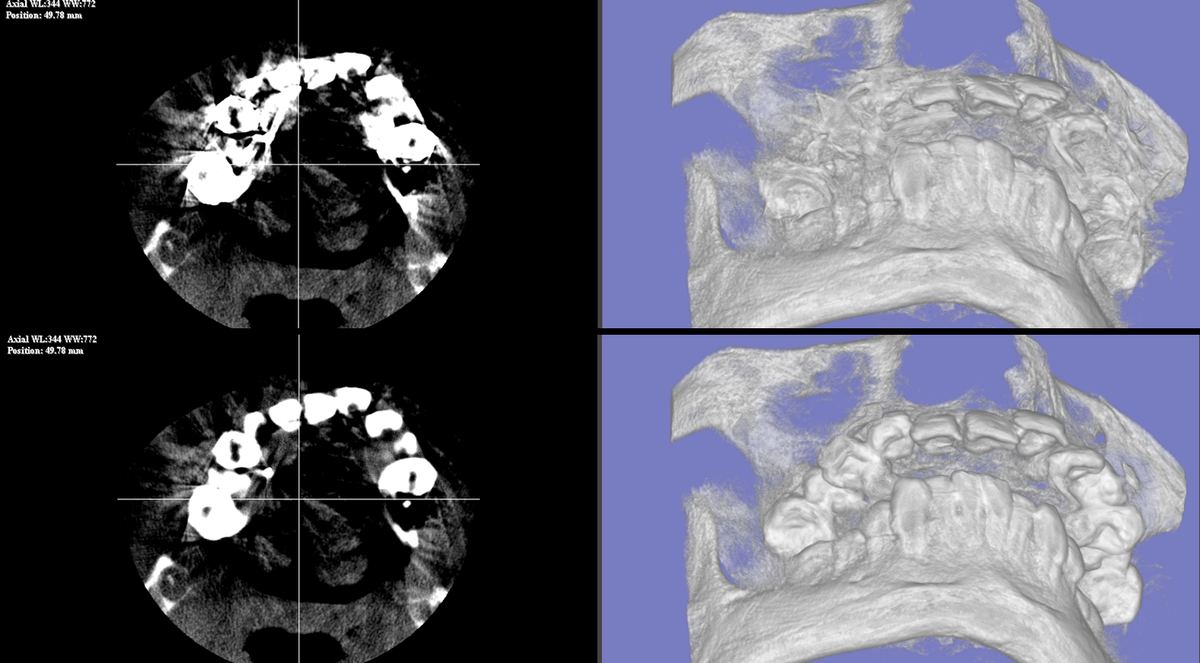

異なる撮影条件・症例においても、一貫してアーチファクト低減と解剖学的構造の復元を確認しています。

※ 画像は実際の処理結果です。症例・GPU環境により処理時間は異なります(目安: 1〜3分)